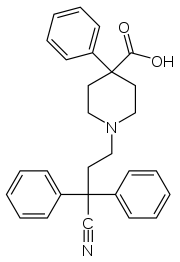

The first fully synthetic opioid was meperidine (later demerol), found serendipitously by German chemist Otto Eisleb (or Eislib) at IG Farben in 1932.[228] Meperidine was the first opiate to have a structure unrelated to morphine, but with opiate-like properties.[199] Its analgesic effects were discovered by Otto Schaumann in 1939.[228] Gustav Ehrhart and Max Bockmühl, also at IG Farben, built on the work of Eisleb and Schaumann. They developed "Hoechst 10820" (later methadone) around 1937.[230] In 1959 the Belgian physician Paul Janssen developed fentanyl, a synthetic drug with 30 to 50 times the potency of heroin.[211][231] Nearly 150 synthetic opioids are now known.[228]